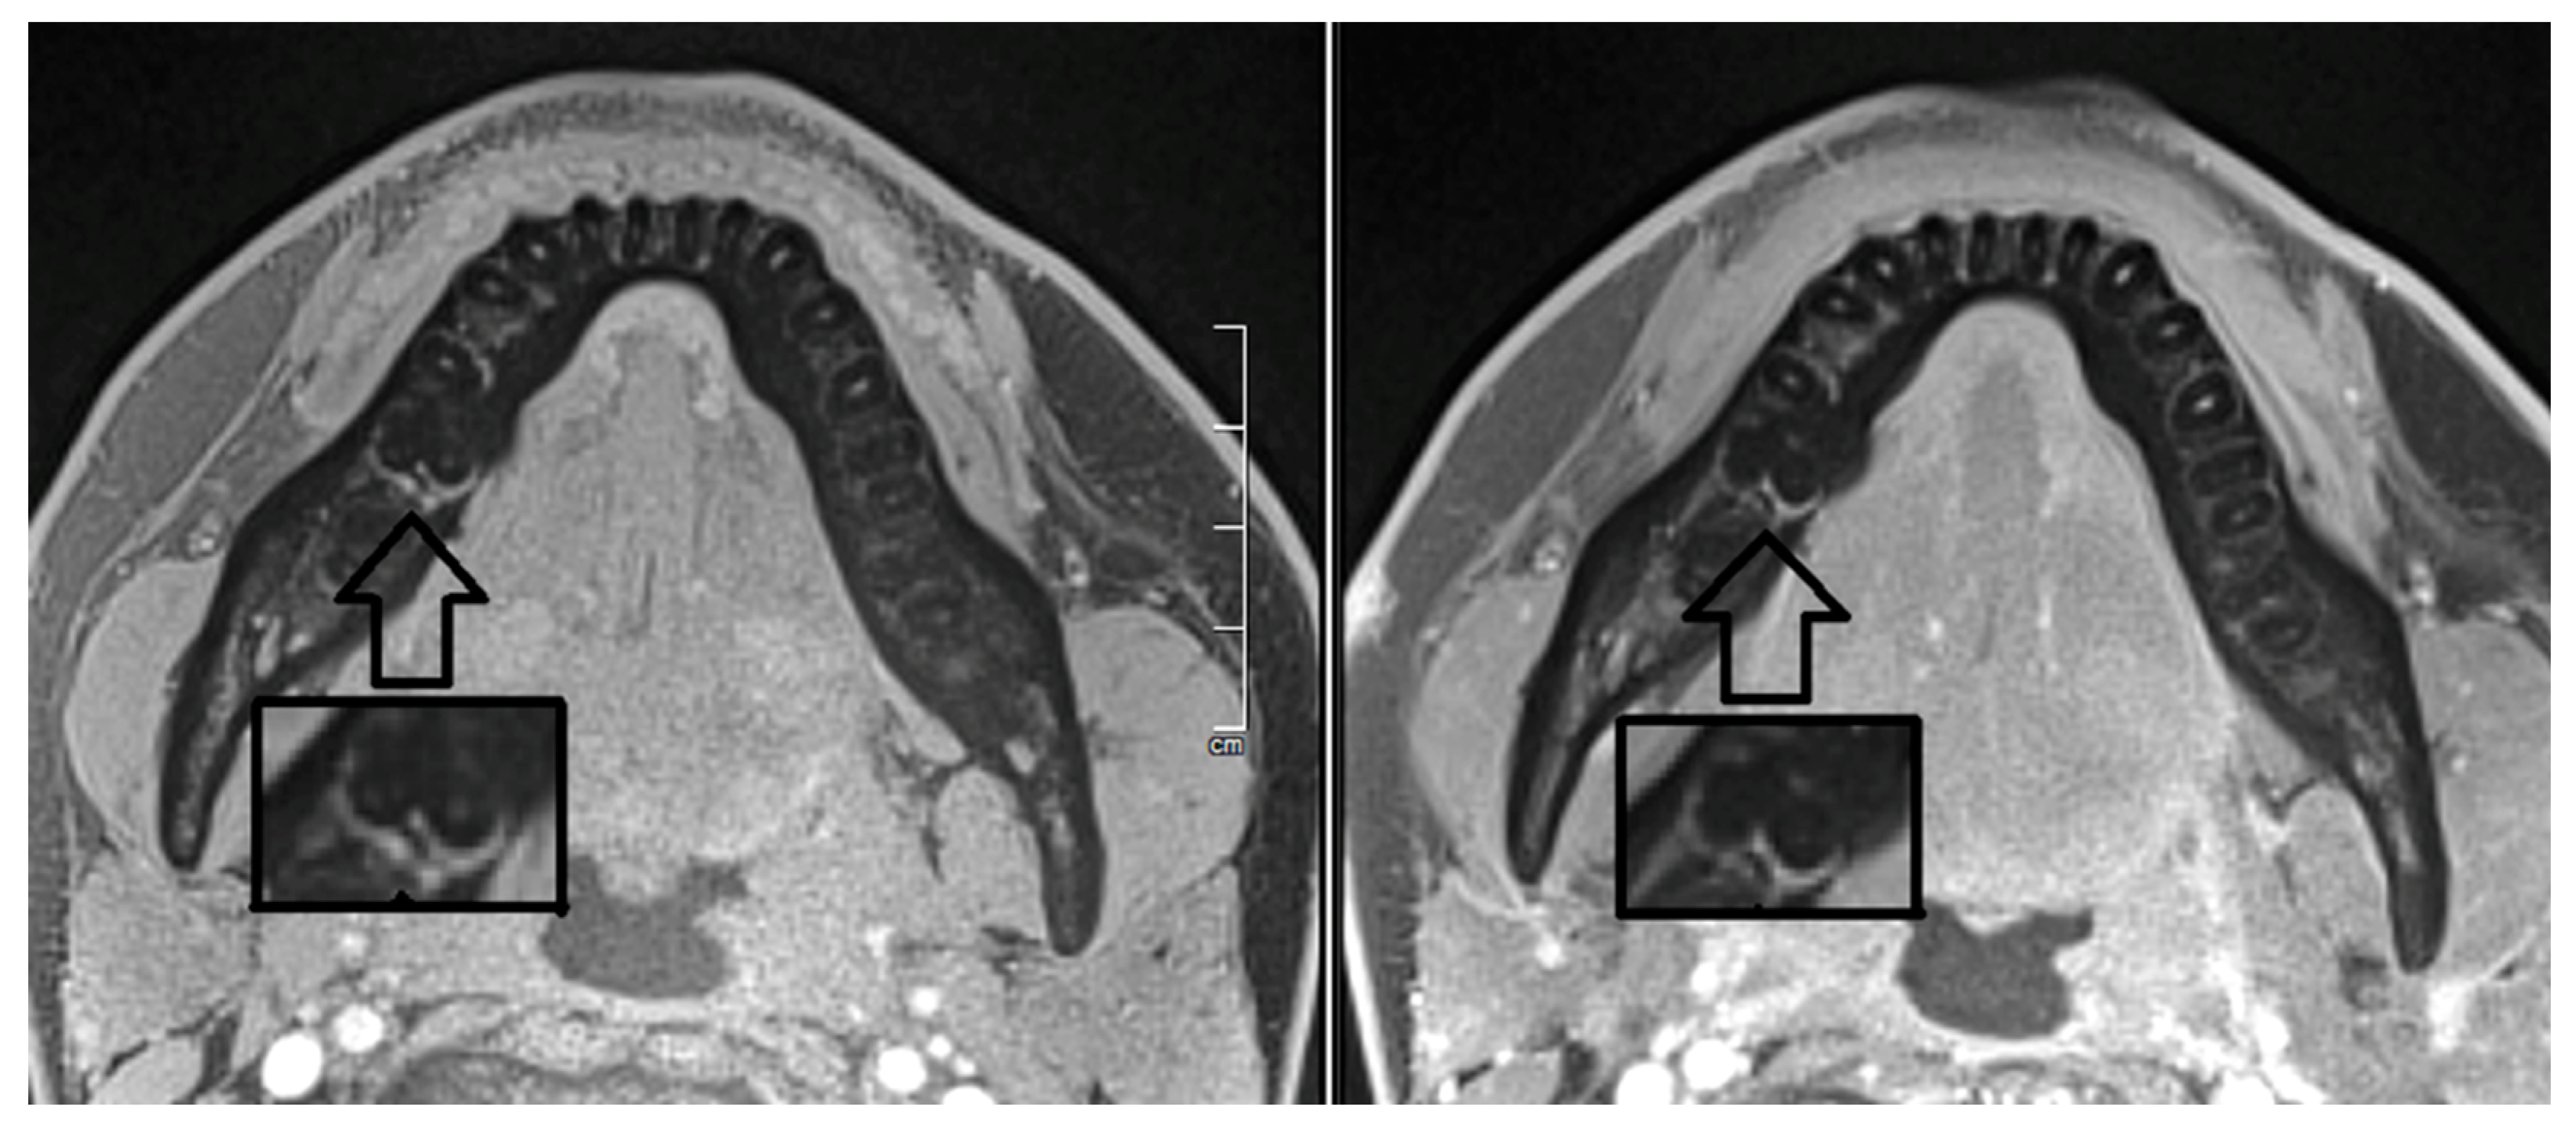

- Assaf, A.T.; Zrnc, T.A.; Remus, C.C.; Khokale, A.; Habermann, C.R.; Schulze, D.; Fiehler, J.; Heiland, M.; Sedlacik, J.; Friedrich, R.E. Early detection of pulp necrosis and dental vitality after traumatic dental injuries in children and adolescents by 3-Tesla magnetic resonance imaging. J. Cranio Maxillofac. Surg. 2015, 43, 1088–1093. [Google Scholar] [CrossRef]

- Kress, B.; Buhl, Y.; Anders, L.; Stippich, C.; Palm, F.; Bähren, W.; Sartor, K. Quantitative analysis of MRI signal intensity as a tool for evaluating tooth pulp vitality. Dentomaxillofac. Radiol. 2004, 33, 241–244. [Google Scholar] [CrossRef] [PubMed]

- Reda, R.; Zanza, A.; Mazzoni, A.; Cicconetti, A.; Testarelli, L.; Di Nardo, D. An Update of the Possible Applications of Magnetic Resonance Imaging (MRI) in Dentistry: A Literature Review. J. Imaging 2021, 7, 75. [Google Scholar] [CrossRef]